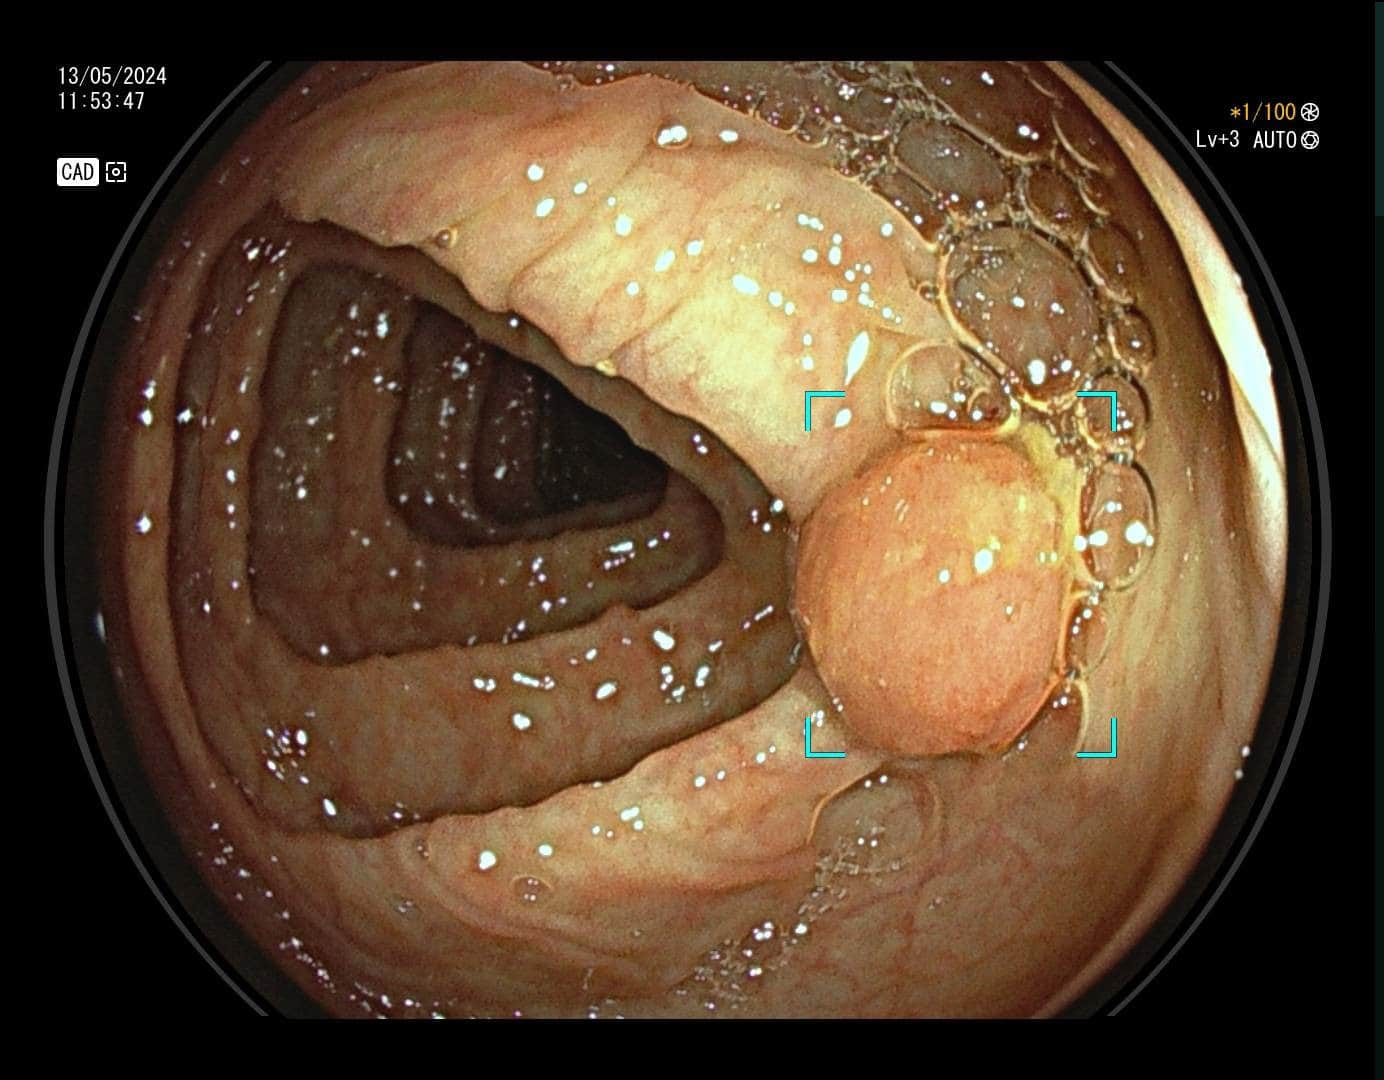

Karcinom debelog crijeva, prema podacima Hrvatskog registra za rak, drugi je po učestalosti uzrok maligne bolesti u žena, a treći u muškaraca. Ova vrsta raka razvija se iz polipa, malih izraslina na sluznici debelog crijeva koje nastaju pod utjecajem okolišnih i/ili genetskih čimbenika. S vremenom polip raste, stanice nakupljaju mutacije, te u konačnici dolazi do razvoja karcinoma. Na sreću, nemaju svi polipi zloćudni potencijal. Kod polipa visokog rizika proces do maligne transformacije je najčešće dugotrajan što nam daje priliku za preventivnim djelovanjem – preventivnu kolonoskopiju preporučuje se učiniti s navršenih 50 godina života, a u slučaju obiteljske sklonosti i u ranijoj životnoj dobi. Cilj pretrage nije dijagnosticirati karcinom već pravovremeno detektirati i ukloniti njegov predstadij – polip.

Kako bi pregled debelog crijeva bio temeljit potrebna je dobra priprema crijeva (očišćenost), no mali i plitki polipi, unatoč optimalnim uvjetima pretrage mogu ostati nezamijećeni, a zbog anatomije crijeva i skriveni iza nabora.